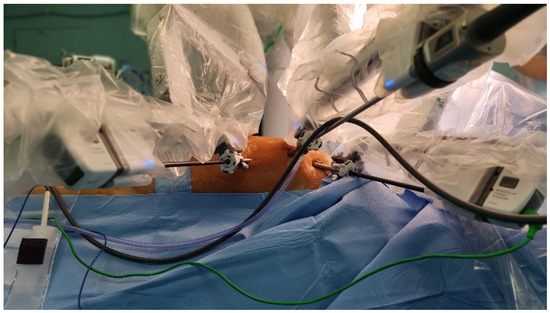

A Single Center Initial Experience with Robotic-Assisted Minimally Invasive Coronary Artery Bypass Surgery (RA-MIDCAB)

Operative Set-Up and Strategy